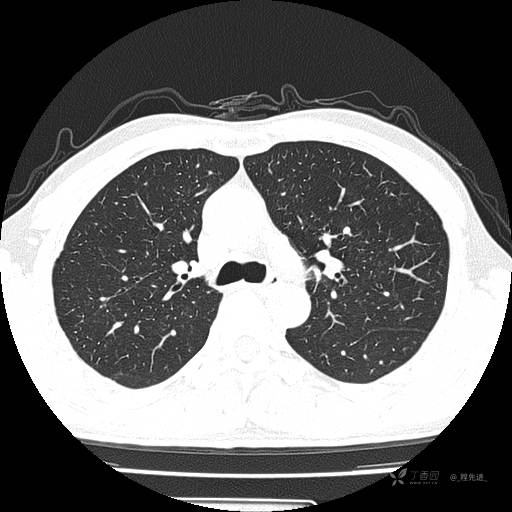

2月特别精彩病例|咳嗽、咳痰20余天,典型病例分享【结果已公布】

呱呱叫了 等 2 位达人已点赞患者性别:男

患者年龄:51岁

主诉:咳嗽、咳痰20余天

简要病史:20余天前开始出现咳嗽、咳痰症状,阵发性刺激性咳,白色粘痰,不易咳出,无发热,无咯血,无恶心、呕吐等不适,未诊治,咳嗽、咳痰症状持续存在。

体格检查:T:36.3 ℃ P:79 次/分 R:20 次/分 BP:128/64 mmHg,神志清楚,呼吸平稳,双肺呼吸音粗,右下肺闻及细湿性啰音。心率79次/分,节律整齐,各瓣膜听诊区未闻及病理性杂音。腹部未见异常,双下肢无水肿。

辅助检查:我院门诊胸部CT示:如下。心电图:窦性心律;正常心电图。